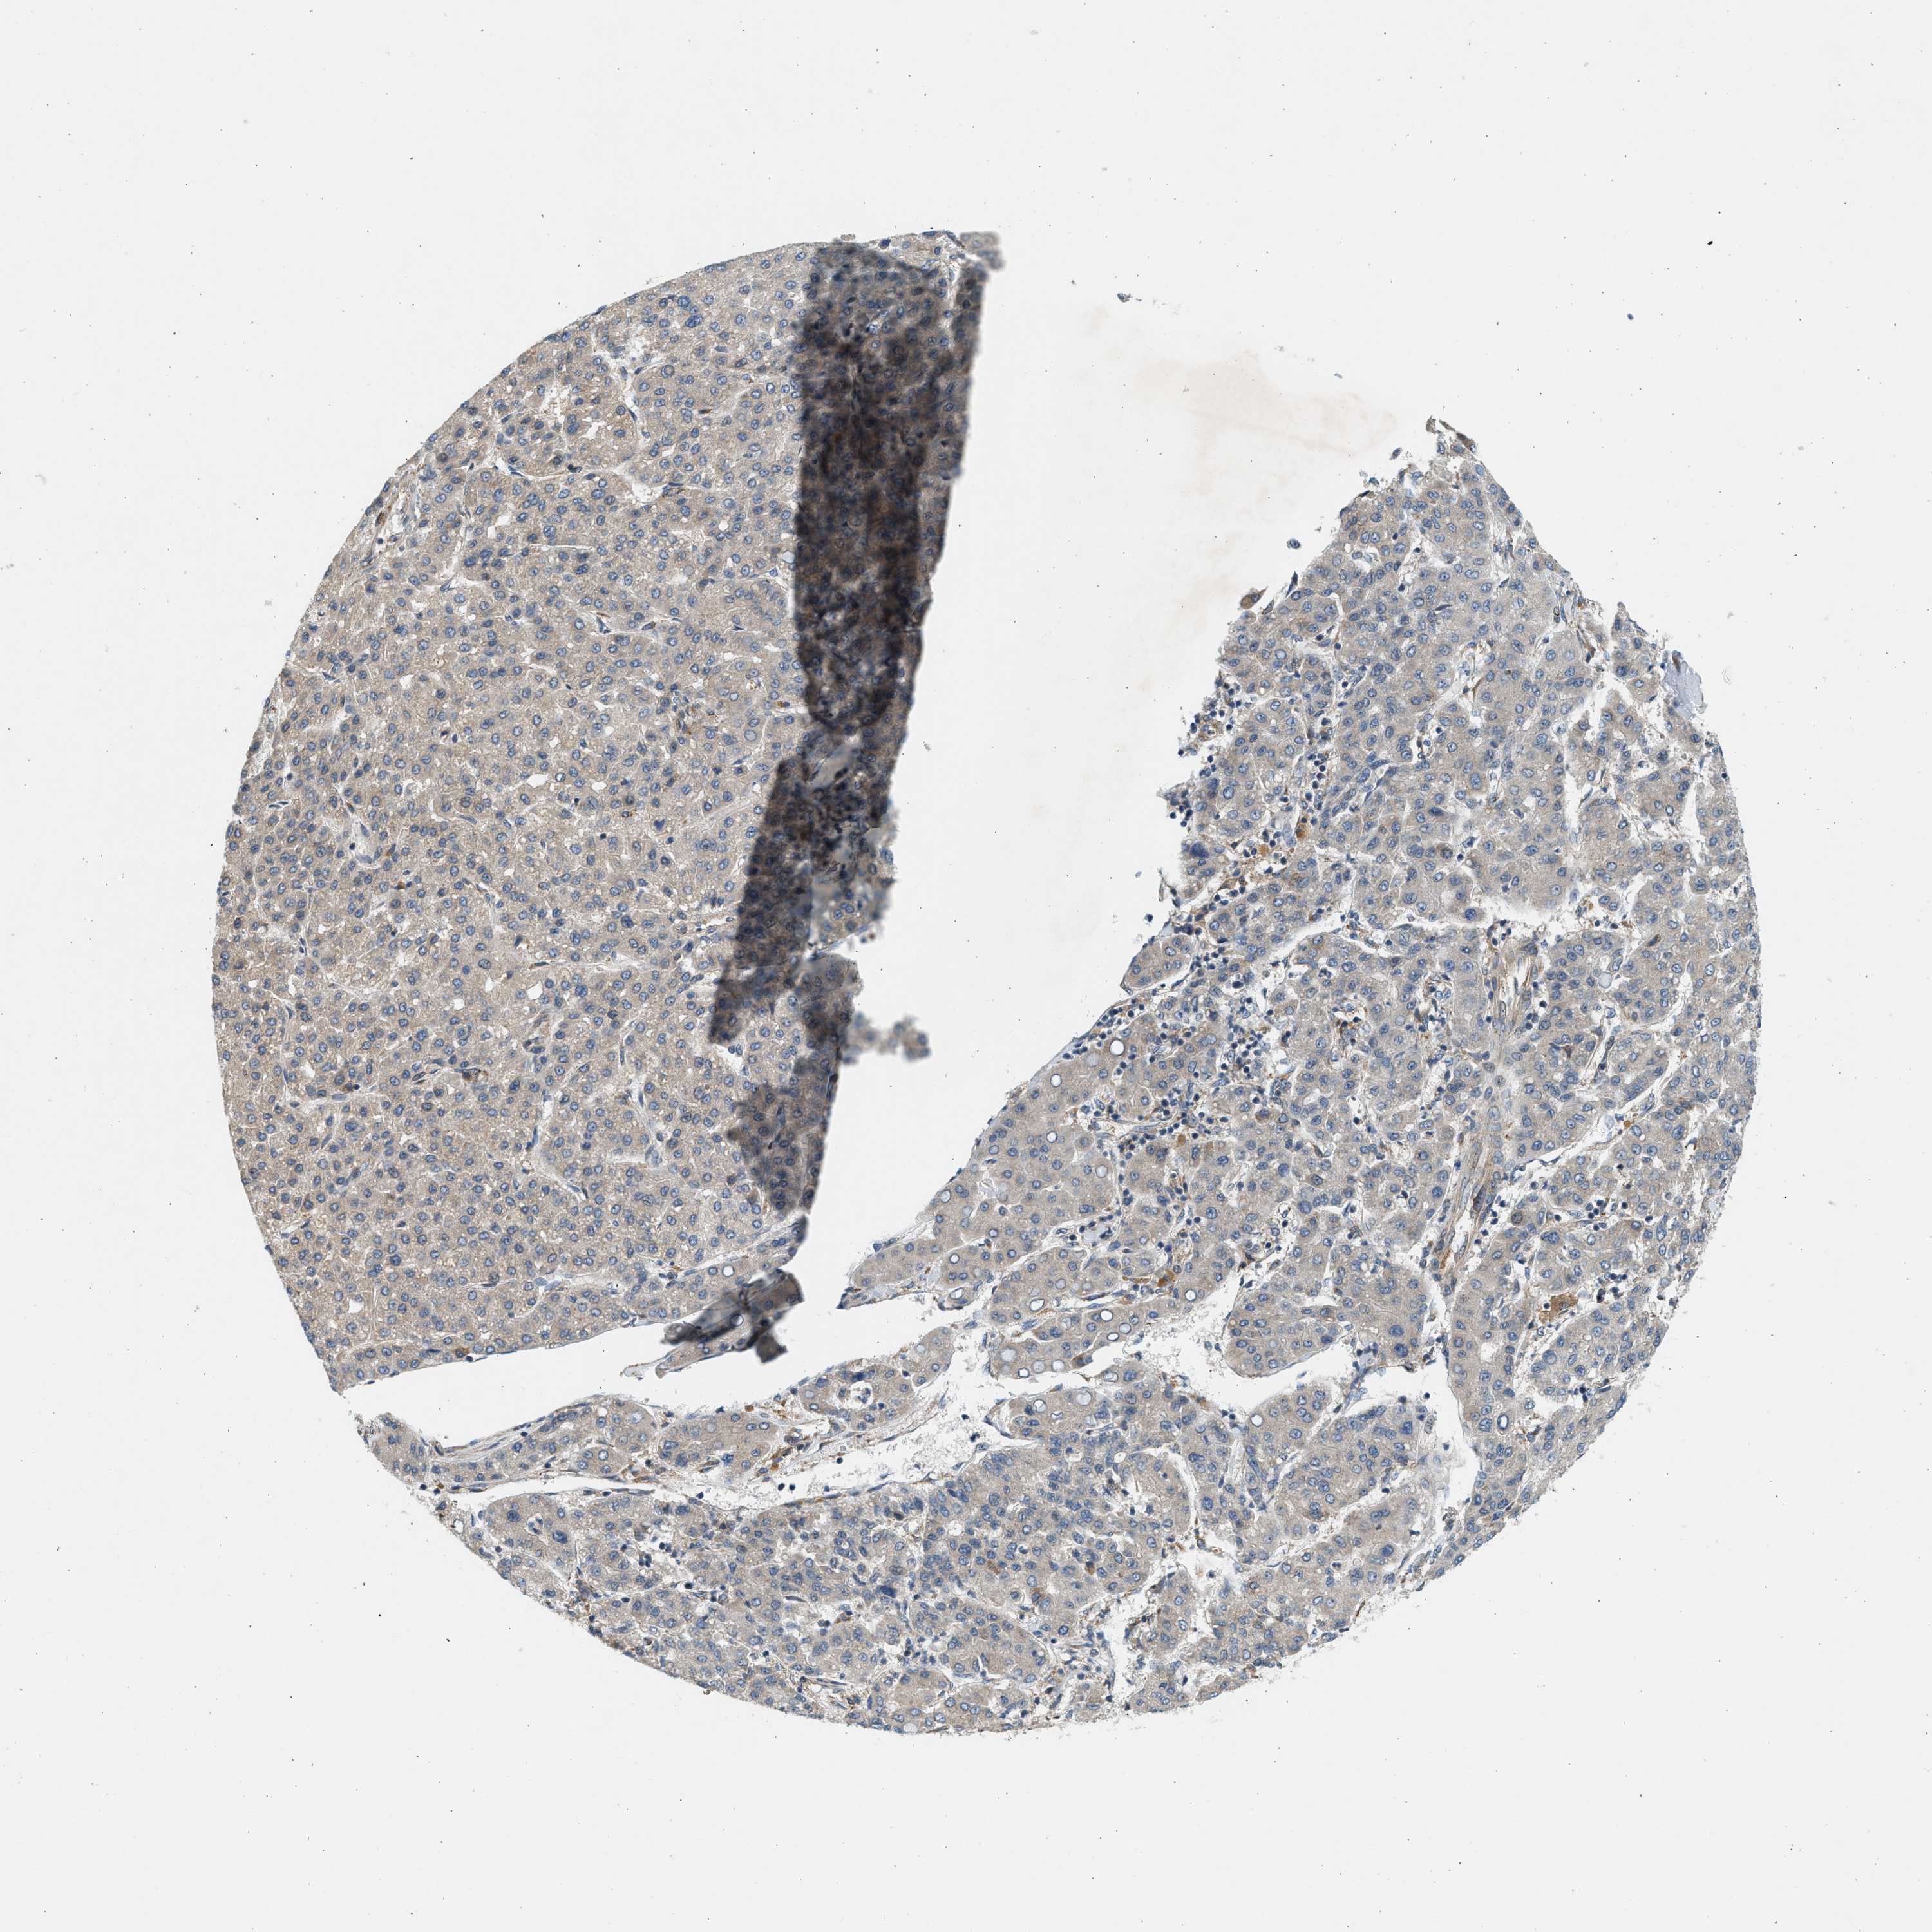

LIVER CANCER - Protein expressioni

A mouse-over function shows sample information and annotation data. Click on an image to view it in a full screen mode. Samples can be filtered based on level of antibody staining by selecting one or several of the following categories: high, medium, low and not detected. The assay and annotation is described here.

Note that samples used for immunohistochemistry by the Human Protein Atlas do not correspond to samples in the TCGA dataset.

Antibody stainingi

Antibody staining in the annotated cell types in the current human tissue is reported as not detected, low, medium, or high, based on conventional immunohistochemistry profiling in selected tissues. This score is based on the combination of the staining intensity and fraction of stained cells.

Each image is clickable and will lead to virtual microscopy that enables deeper exploration of all samples and also displays staining intensity scores, fraction scores and subcellular localization as well as patient and tissue information for each sample.

Antibody HPA016459

Staining

High

Medium

Low

Not detected

Intensity

Strong

Moderate

Weak

Negative

Quantity

>75%

75%-25%

<25%

None

Location

Nuclear

Cytoplasmic/membranous

Cytoplasmic/membranous,nuclear

Cholangiocarcinoma

Carcinoma, Hepatocellular, NOS